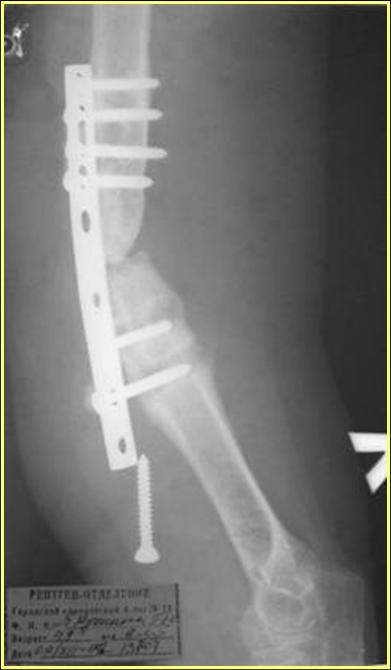

Рентгеновская версия реконструкции. хронология:

после операции, 2 мес. после операции, через 1 год

Движения в полном объеме восстановлены к 2 мес. после операции. Если надо могу показать мультик. Сейчас уже прошло более 3 лет, больная не

показывается. Успехов ЛАФ.